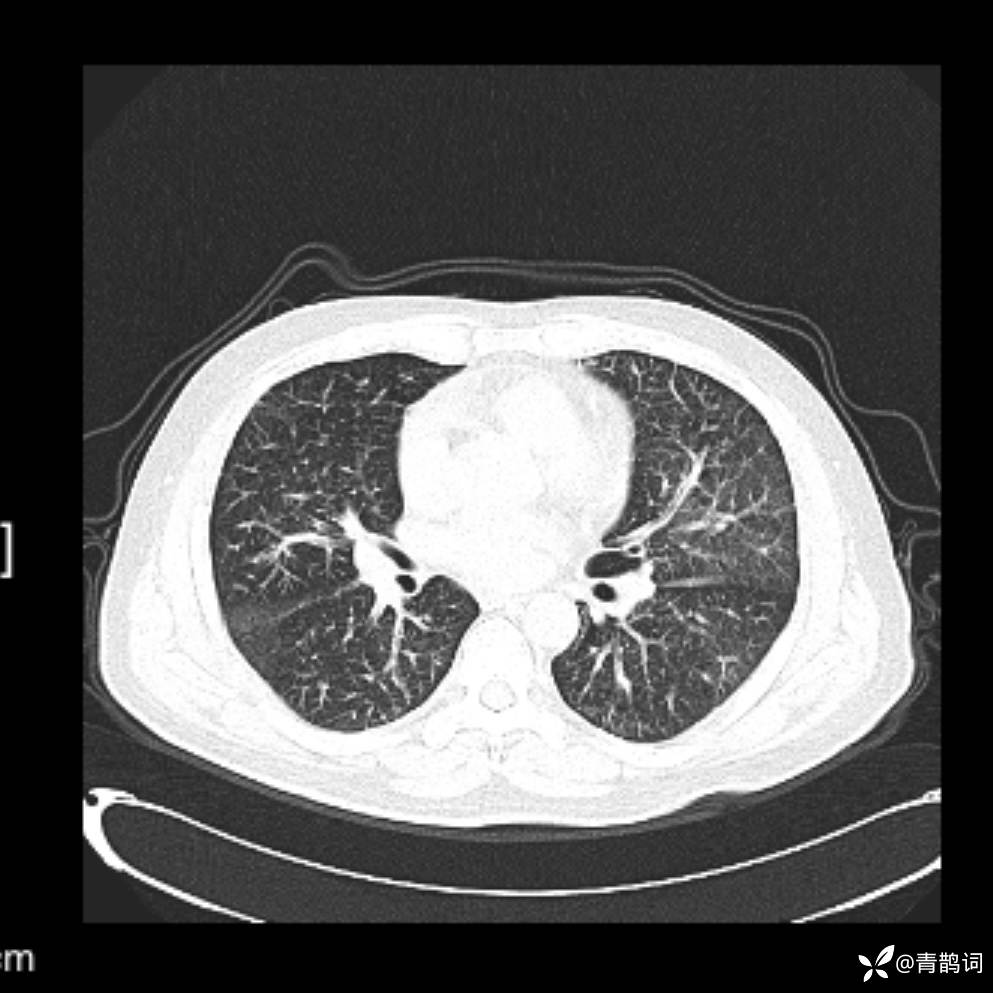

患者年龄:30岁。

患者性别:男。

简要病史:左颜面部肿胀2年,反复咳嗽咳痰,逐渐加重。

辅助检查

结合病史及影像学表现,期待评论区各位老师各抒己见~